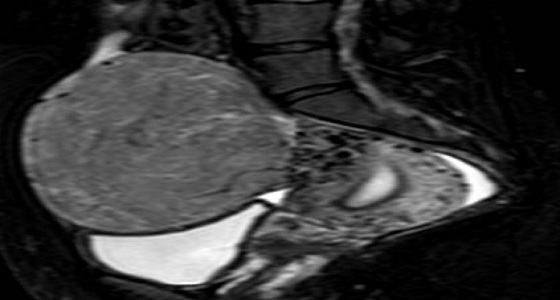

استئصال ورم كبير دون جراحة بألماني عسير

استئصال ورم من رحم فتاة 24 عاما بالمدينة المنورة